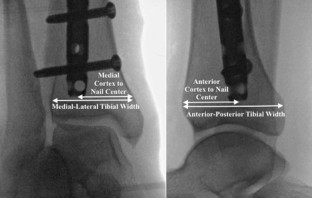

An intramedullary nail was placed in 14 skeletally mature legs. This included 8 patients with mid-shaft tibial fractures and 6 intact cadaveric legs. Each nail was a titanium cannulated tibial nail, size 10- or 11-mm. The nails were placed using a suprapatellar or transpatellar approach with an ideal starting point. All legs received post-nail insertion CT scans and fluoroscopy. The main outcome measure was the terminal location of the nail just proximal to the distal tibial physeal scar, as seen on axial CT and fluoroscopic views of the ankle (mortise and lateral). The end-point was measured as the (1) ratio of medial–lateral tibial width (ML ratio) and (2) ratio of anterior–posterior tibial width (AP ratio). Two-tailed Welch’s t tests were used to compare the actual, observed position of the nail to the hypothesized center–center position (H0 = ML and AP ratio of 0.5).

All enrolled patients (n = 8) and cadaveric legs were included (n = 6). On axial CT, the average distance from the medial tibial cortex to the nail center as a ratio of medial–lateral tibial width was 0.63, 95% CI 0.60–0.67, p < 0.001 (Patient = 0.60, 95% CI 0.55–0.64, p = 0.001) (Cadaver = 0.68, 95% CI 0.64–0.73, p < 0.001). On fluoroscopic mortise views, the distance from the medial cortex to the nail center as ratio of medial–lateral tibial width was 0.64, 95% CI 0.60–0.67, p < 0.001 (Patient = 0.61, 95% CI 0.56–0.65, p < 0.001) (Cadaver = 0.67, 95% CI 0.63–0.72, p < 0.001). The AP ratio was not significantly different from 0.5 on either axial CT or fluoroscopic mortise views (p > 0.05).